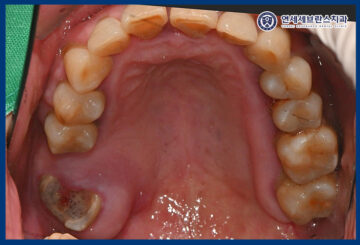

확인해 보니,

오른쪽 아래 통증을 느끼는 부위의

뿌리 끝 염증이 진행되어 있었는데요.

이로 인해 잇몸이 붓고

심한 압통이 동반되었으며,

일상적인 식사나 저작 시에도

큰 불편을 겪고 계셨는데요.

또한 다른 부위들도 치아가 부러지거나

충치가 생겨 치료가 필요한 부위가 많았습니다.